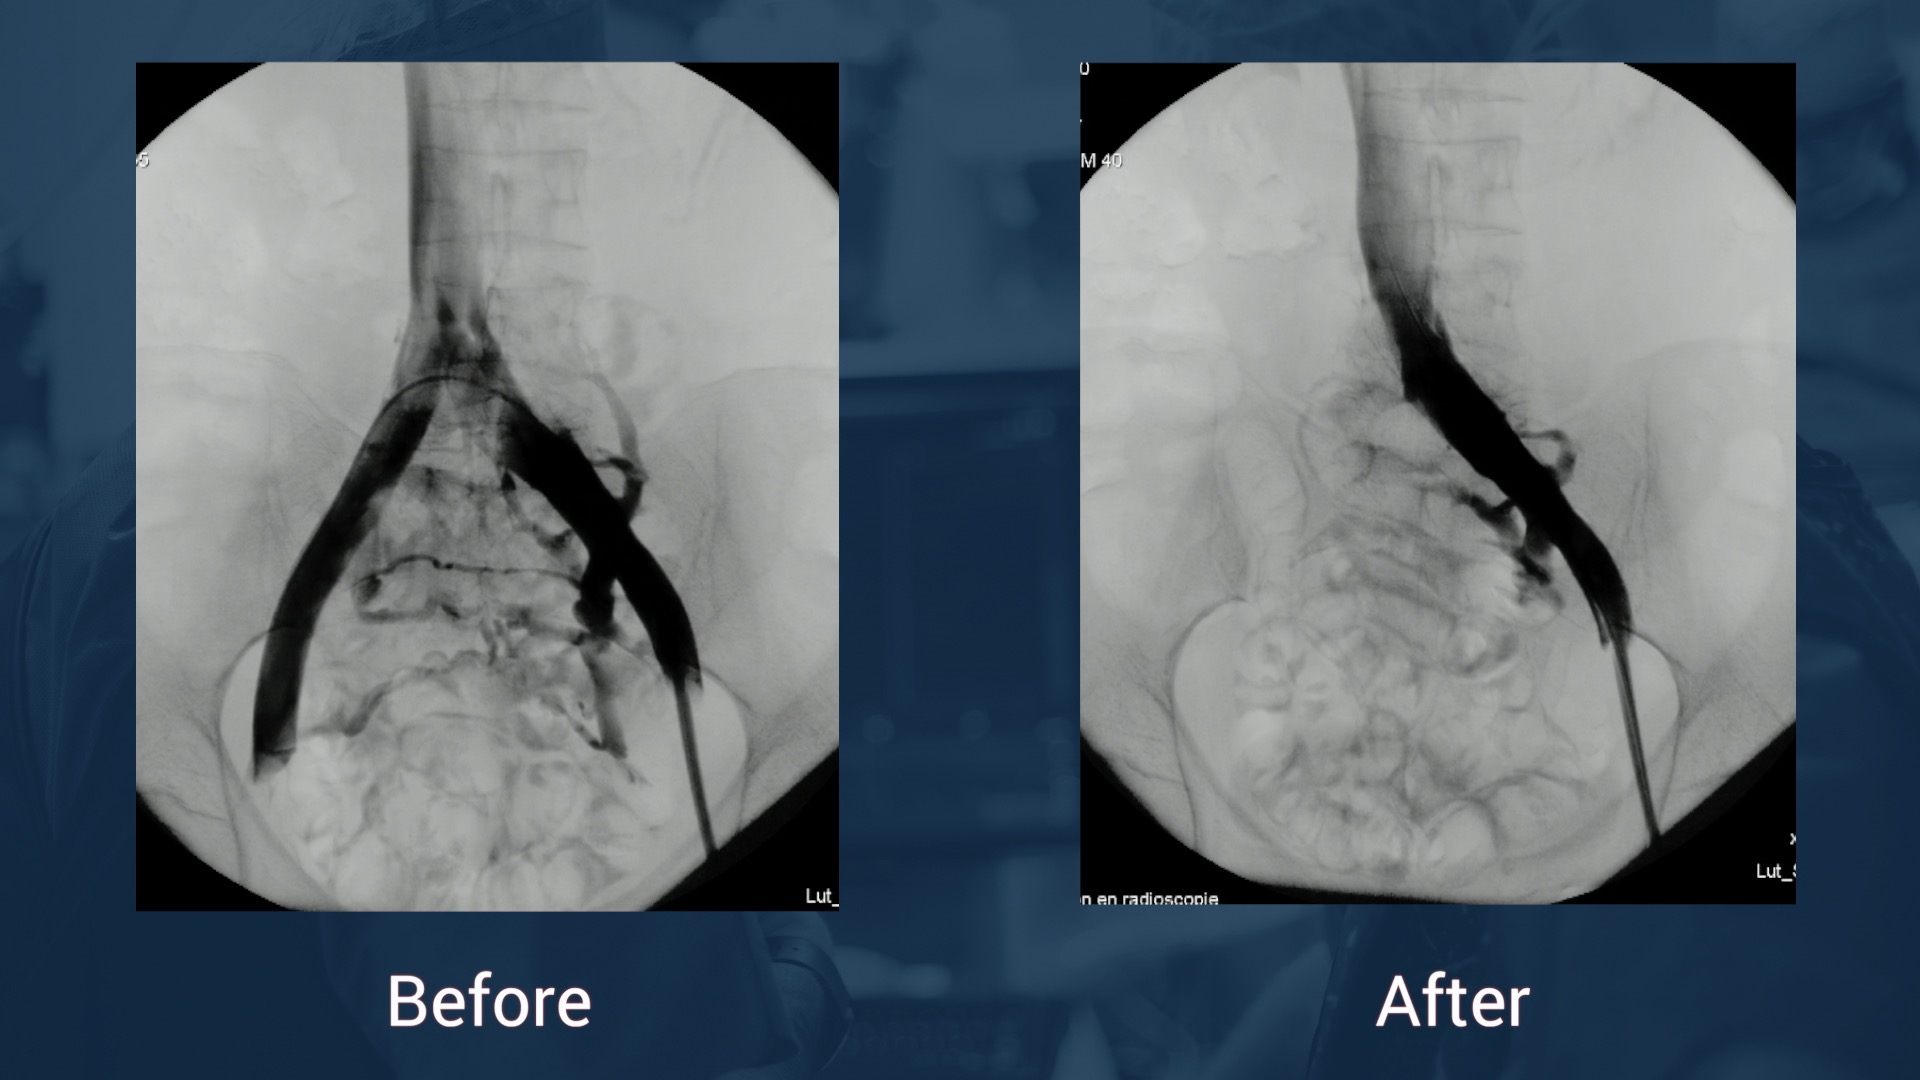

12.47 Case in box n°1: May-Thurner syndrome

12.57 Case in box n°2: May-Thurner syndrome

13.33 Case in box n°3: Left femoro iliac vein recanalization and stenting

Panel discussion

13.41 Case in box n°4: Left femoro iliac vein recanalization and stenting

Left iliac venous occlusion

Dr Black, Dr De Graaf, Dr Hartung & Dr O'Sullivan